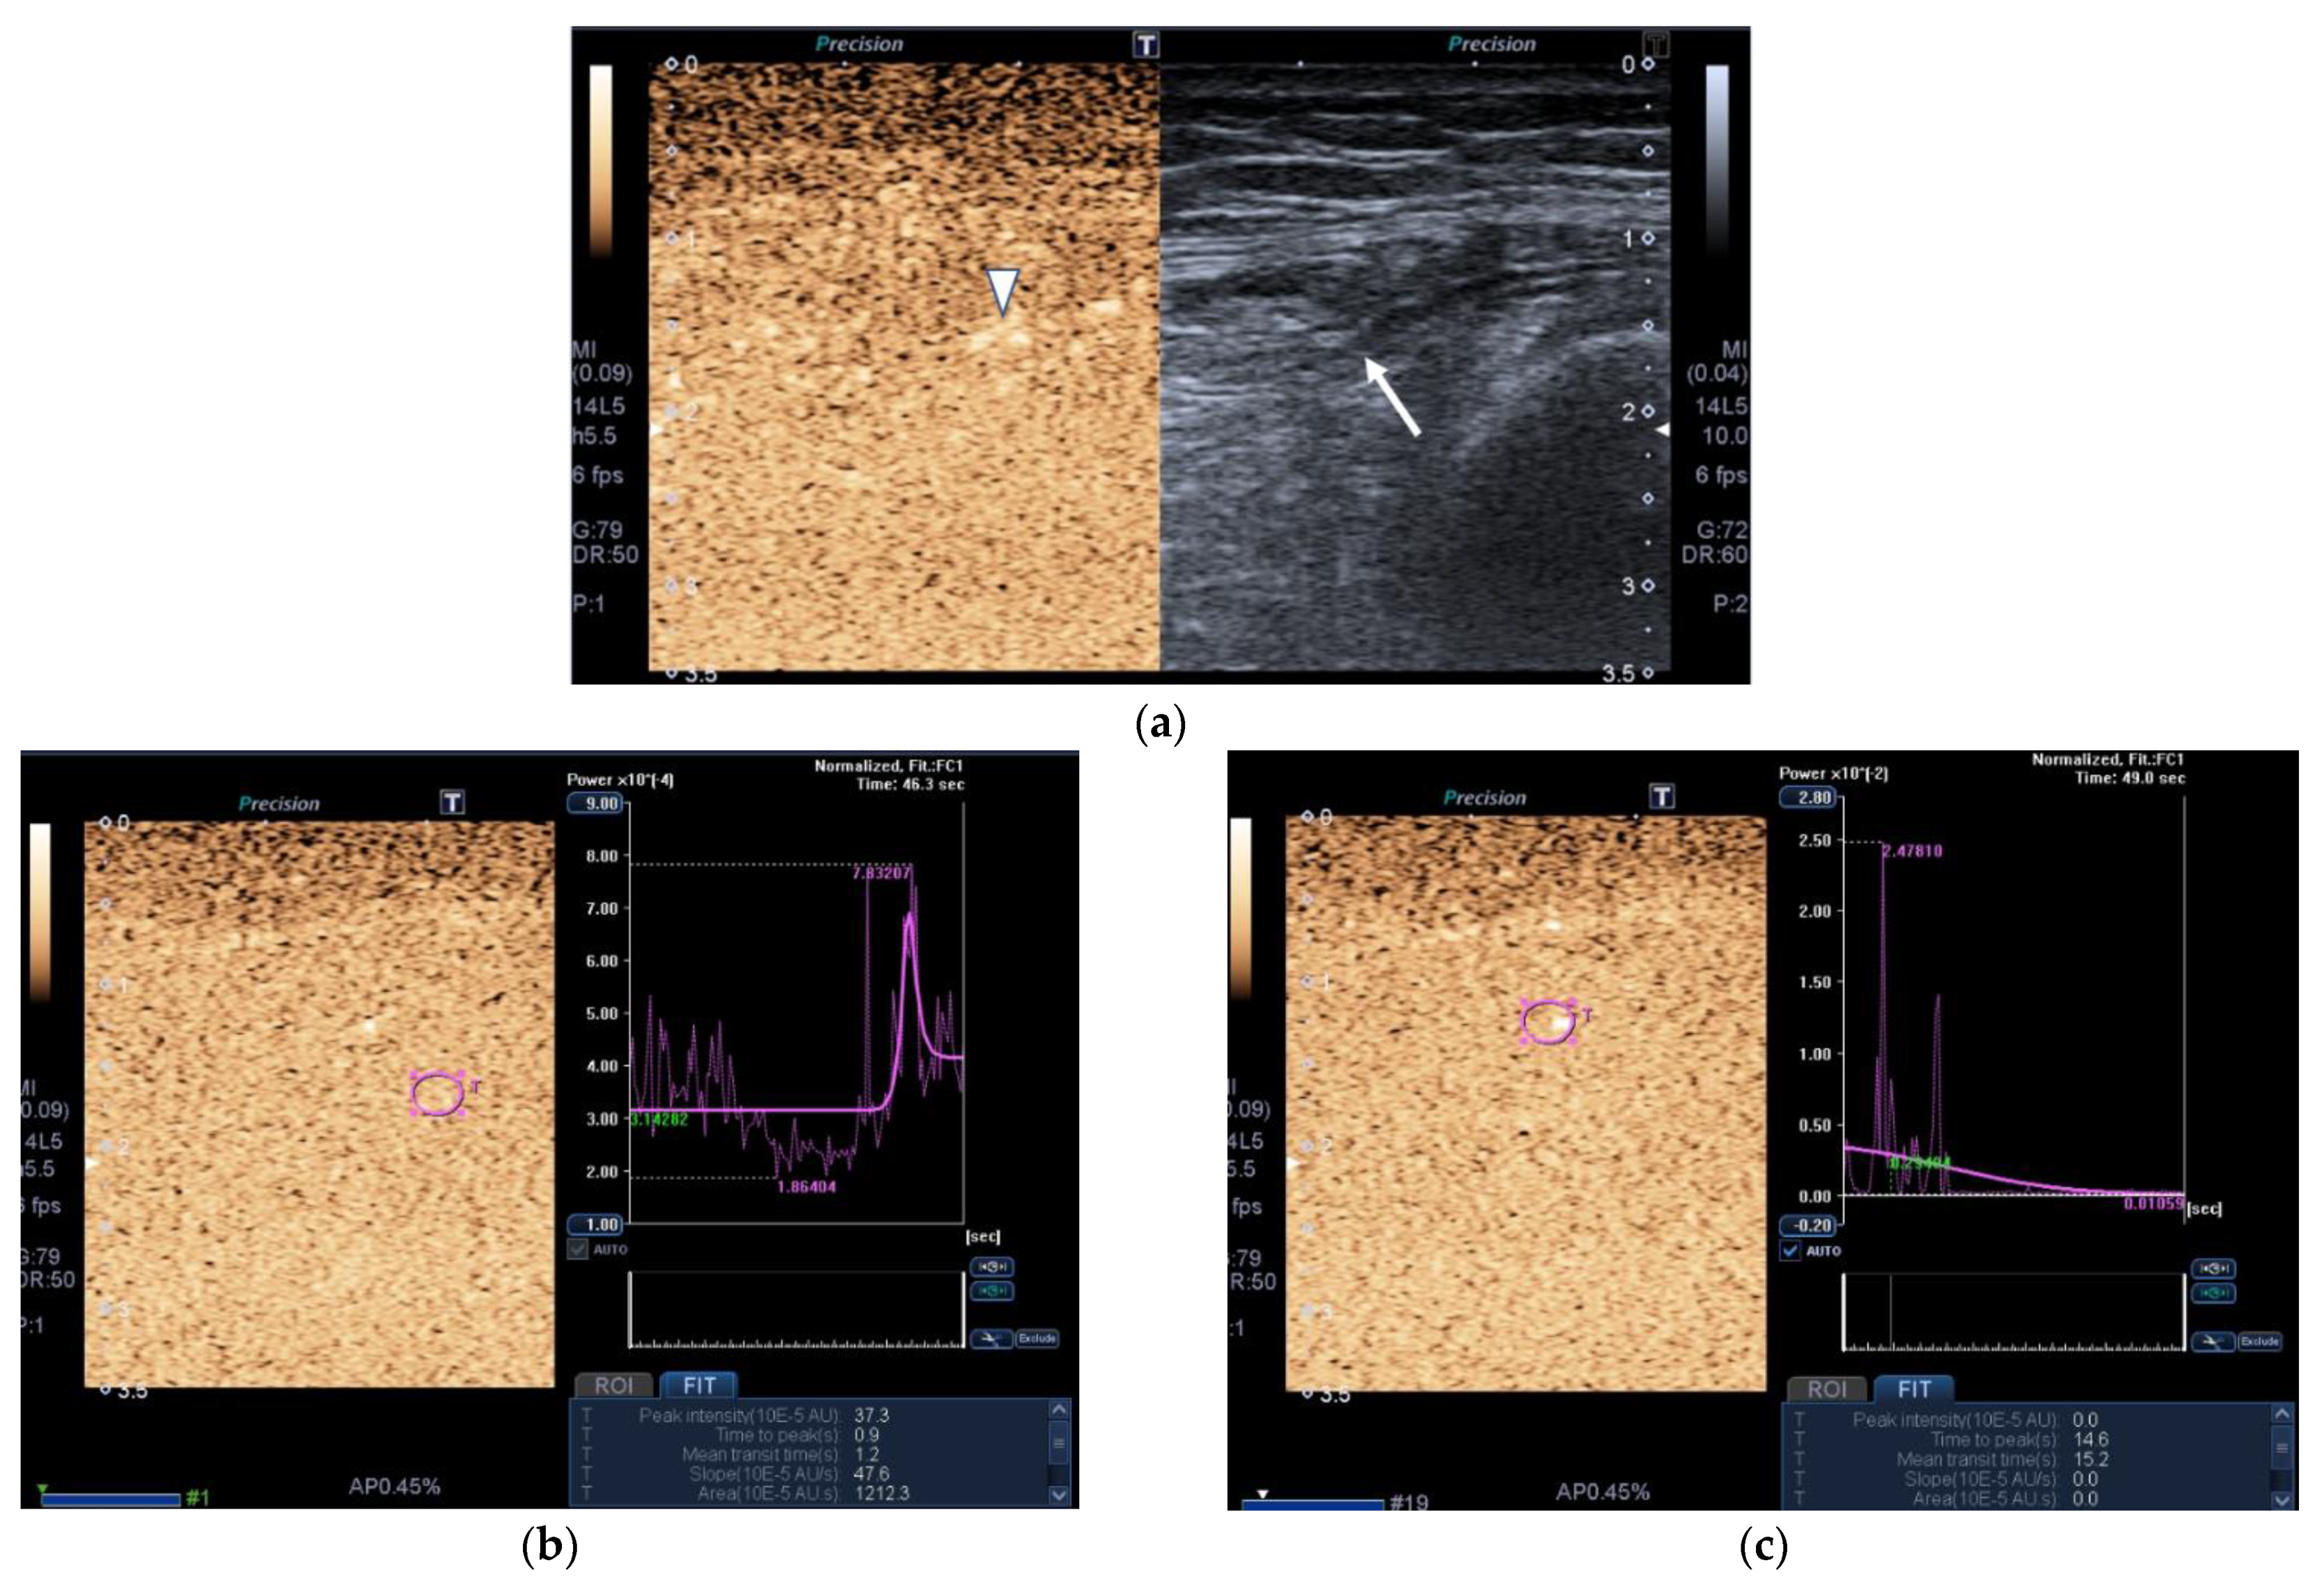

SMI images of a patient and a healthy control are displayed in Figure 2.

Figure 2.

Transversal QRF muscle US scan and the superb microvascular imaging (SMI) built-in software that indicates microvascularization. (a)Transversal QRF muscle (arrow) US scan, femur (arrowhead). SMI image shows dot-like vessels and a penetrating vessel (star) for a matched healthy control (60 years old). (b) Transversal QRF muscle (arrow) US scan, femur (arrowhead); subcutaneous edema with intramuscular and interfacial fluid (thick arrow). SMI image shows dot-like vessels for a patient with multiorgan failure (58 years old). (c) Transversal QRF muscle (arrow) US scan, femur (arrowhead). SMI image shows minimal linear vessels for another patient with multiorgan failure (51 years old).